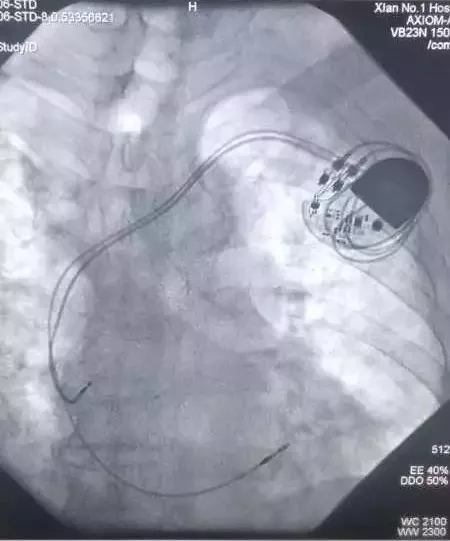

CCU成功实施啄木鸟 首例双主动电极抗核磁起搏器植入术